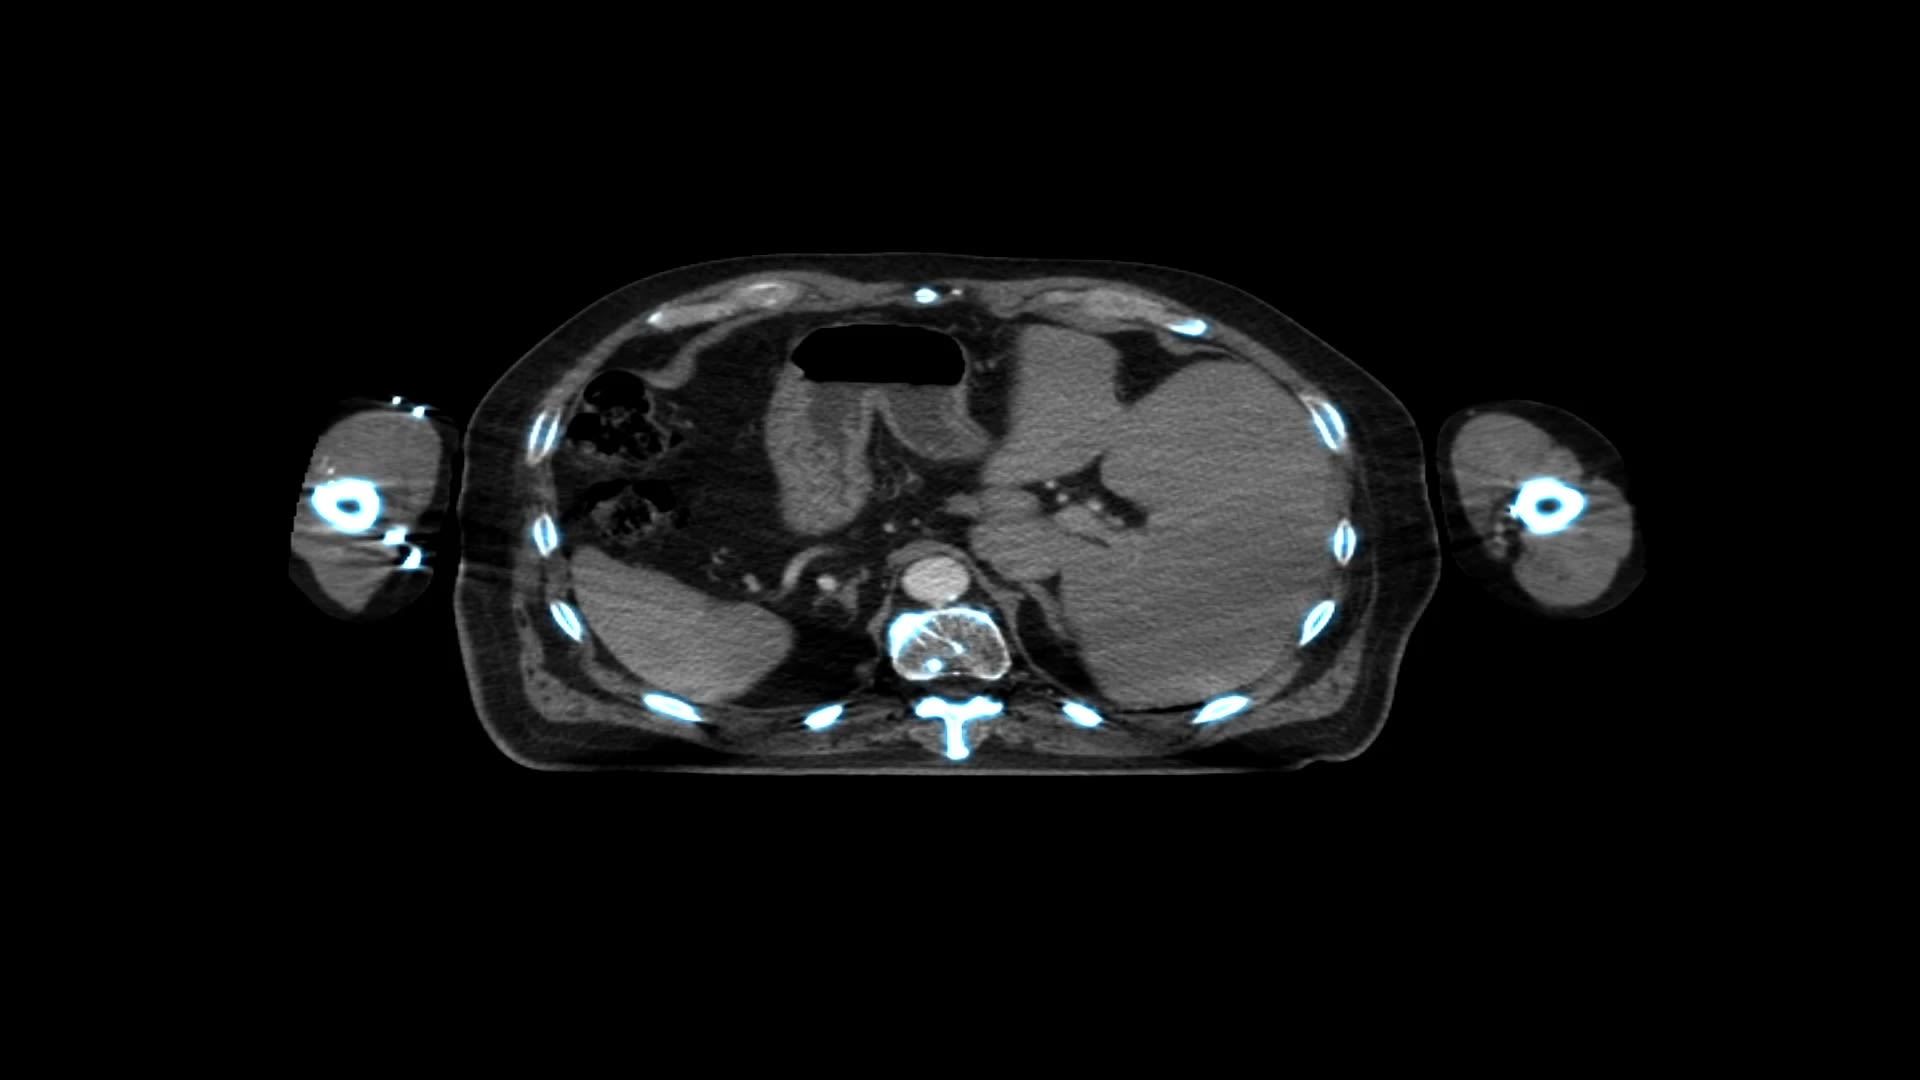

The last few decades have seen the evolution of conformal external beam radiotherapy (CRT), which uses computed tomographic (CT) images to precisely delineate a target, with X-ray beams from different directions targeting a tumour. Prior to this, radiotherapy beams were delivered using minimal image guidance as simple square or rectangular fields.

Conformal radiation therapy (CRT)

(Image credit: JazzIRT/Getty Images)

IMRT

Intensity-modulated radiotherapy (IMRT) is an extension of CRT, in which individual beams can be modified to produce doses of varying intensity, sculpting and shaping the beam to produce a concave shape. This reduces the dose and, consequently, the toxicity, to nearby normal tissues.

Intensity-modulated radiotherapy (IMRT)

(Image credit: Mark Kostich/Getty Images)

VMAT

Unlike IMRT, which uses multiple different beams of different intensities to produce an inhomogeneous dose distribution, volumetric modulated arc therapy (VMAT) can deliver dose continuously as the gantry of the linear accelerator (LINAC) rotates around the patient, hence reducing treatment time and minimising the overall dose. It is being increasingly used for everyday radiotherapy treatment and is especially useful when a tumour is next to a critical organ at risk.

Volumetric modulated arc therapy (VMAT)

(Image credit: Mark Kostich/Getty Images)